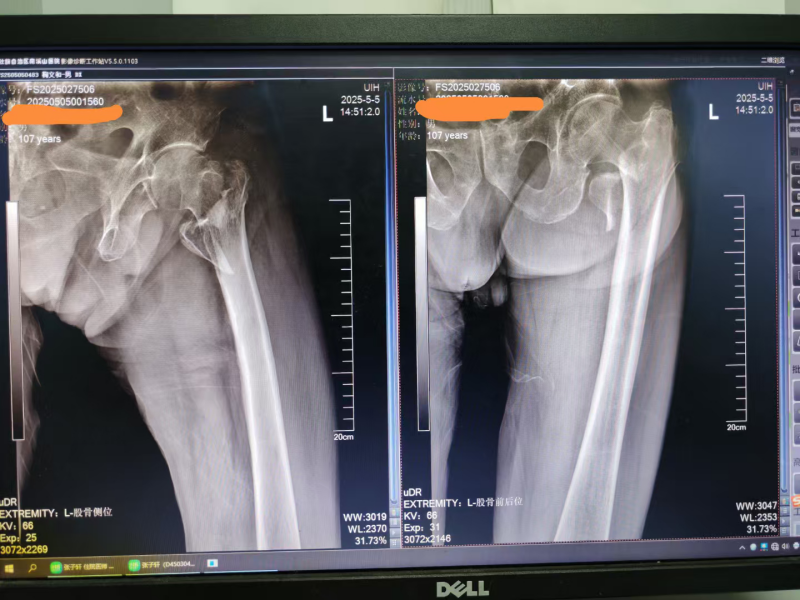

患者术前的X光片